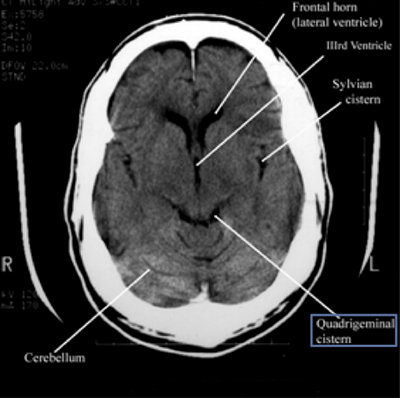

Step 4: Ventricles

Ventricles

Examine for IIIrd, IVth and lateral ventricles for dilation or compression/shift.

Pathologic processes cause dilation (hydrocephalus) or compression/shift. Communicating vs. Non-communicating. Communicating hydrocephalus is first evident in dilation of the temporal horns (normally small, slit-like). The lateral, IIIrd, and IVth ventricles need to be examined for effacement, shift, and blood.